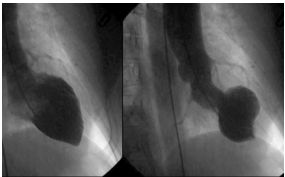

Ventriculografia a seguir:

CARABALLO, K Editoriales Sociedad Interamericana de Cardiología. 15.04.19.

Sobre o caso clínico apresentado e a principal hipótese diagnóstica, para as afirmações a seguir, assinale (V) para a verdadeira e (F) para a falsa.

( ) As anormalidades de parede, ao ecocardiograma, podem acometer território de mais de uma coronária. ( ) Pode ocorrer aumento dos níveis da troponina sérica. ( ) Um gatilho de estresse físico ou emocional está presente na maioria dos pacientes, mas não é obrigatório para o diagnóstico. ( ) A ressonância magnética cardíaca é necessária para o diagnóstico.

As afirmativas são, respectivamente,